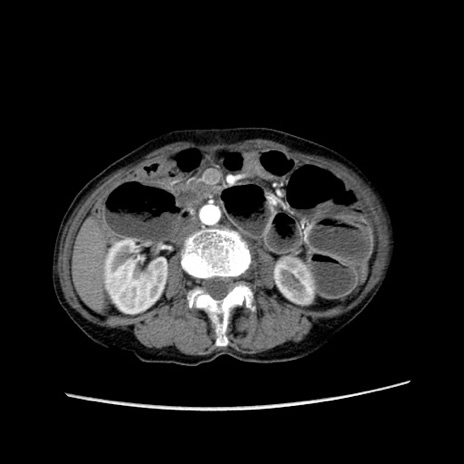

症例25(横断像)

【症例】80歳代女性

【主訴】胸のつかえ感

【現病歴】約9時間前に食後から胸のつかえた感じあり、嘔吐あり、来院。

【既往歴】胃癌(全摘)、胆摘、虫垂炎

【身体所見】心窩部に圧痛あり、反跳痛なし。

【データ】WBC 5700、CRP 0.05